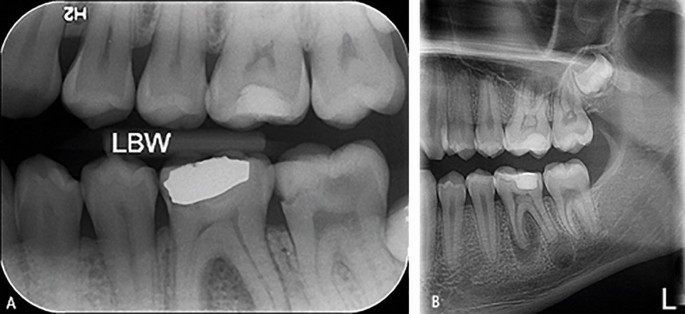

Radiografiile intraorale sunt o modalitate de imagistică care se concentrează pe zone specifice din gura pacientului, oferind imagini detaliate ale dinților, rădăcinilor acestora și a altor structuri orale. Aceste radiografii sunt utilizate pentru diagnosticarea cariilor, afecțiunilor pulpare, bolii parodontale și a altor probleme dentare. Există mai multe tipuri de radiografii intraorale, fiecare având aplicații specifice.

Diagnosticul cariilor dentare: Aceste radiografii ajută la identificarea cariilor și la planificarea tratamentelor de restaurare.

Endodonție: Radiografiile intraorale sunt utile în endodonție pentru a identifica leziuni pulpare și pentru a ghida tratamentele de canal radicular.

Extracții dentare: În cazul extracțiilor dentare, radiografiile intraorale pot ajuta medicul stomatolog să evalueze rădăcinile dentare și să planifice procedura.